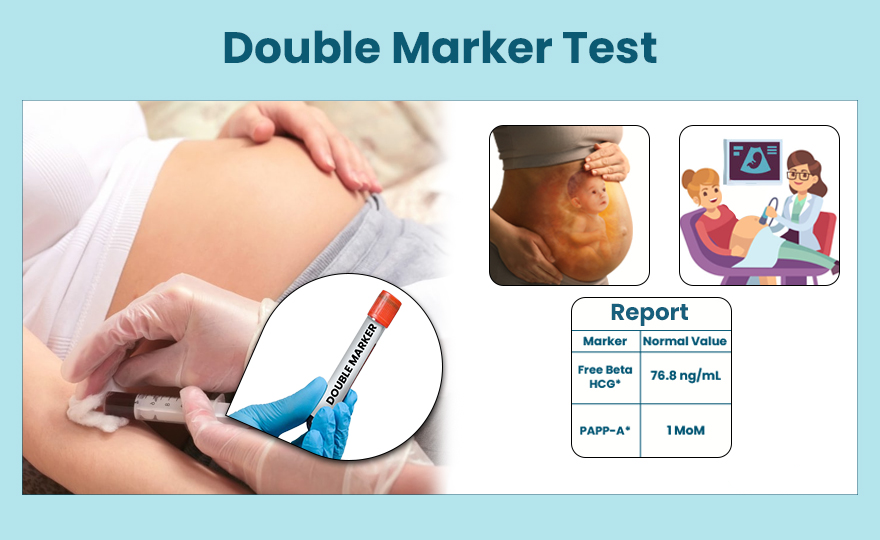

Advanced genetic testing and molecular diagnostics.